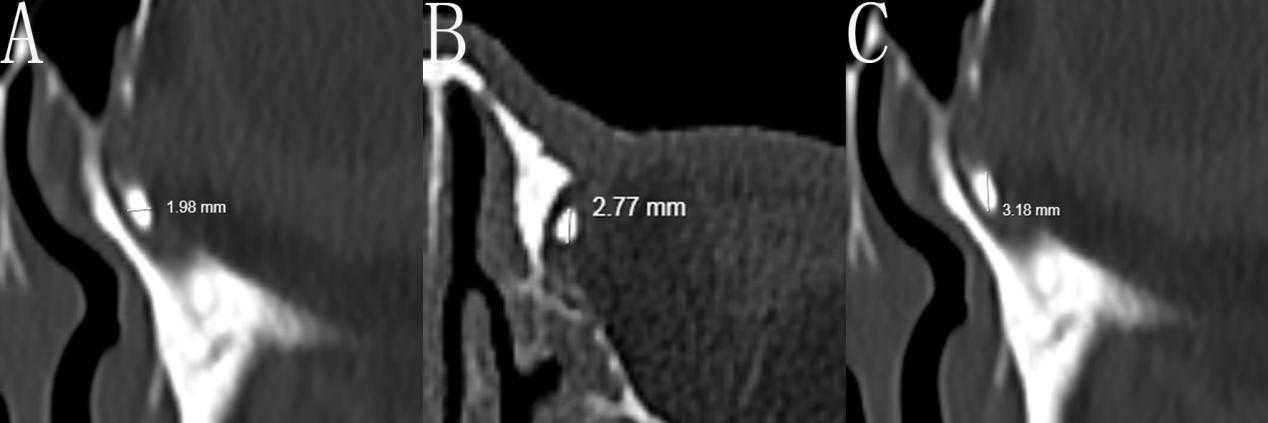

本研究应用CT-DCG用来评估泪道引流系统,采用碘普罗胺(优维显Ultravist370)作为显影剂进行螺旋CT检查:在泪道内注入显影剂之前,通过轻轻按摩内眦清除泪囊内分泌物以便于显影剂进入;用泪道冲洗针头通过下泪小点将显影剂缓慢地通过泪小管、泪总管进入泪囊,直至显影剂从上泪小点溢出即完成显影剂的注入。立刻使用德国西门子螺旋CT仪(SOMATOM Emotion 16)在水平面进行螺旋CT检查(采用0.75 mm准直扫描,分别用0.75 mm层厚、0.5 mm层间距)。然后通过使用图像处理重建生成冠状面图像,由放射科医生测量泪囊的三维最大直径,包括水平径、前后径和垂直径(如图1所示)。测量采用边缘到边缘的测量方法,对每个直径测量三次,并取三次测量的平均值作为最终的测量结果。同时满足以下3个条件标准将泪囊视为小泪囊:1) 水平径≤3 mm;2) 前后径≤3 mm;3) 垂直径≤6 mm。

图1 CT-DCG测量小泪囊

Figure 1 CT-DCG measures the small lacrimal sac

本研究共纳入69例患者(69只眼),其中5例患者未能完成术后9个月随访而未纳入。2例术中通过直径3 mm的剥离子对比核对不符合小泪囊诊断而未纳入,1例患者在术后1个月人工泪管脱出而未纳入。最终纳入61例患者,平均年龄为(55.31±12.28)岁(范围为27~75岁)。其中女性40例,男性21例,右眼33眼,左眼28眼。CT-DCG显示纳入患者的泪囊三维情况:泪囊水平径为(2.58±0.34)mm、前后径为(2.55±0.31)mm、垂直径为(4.43±0.66)mm。所有患者均顺利完成开放泪总管平面的En-DCR联合BSTI术治疗。人工泪管于术后3个月在门诊内镜室取出。经过9个月系统随访,基于既定成功率评定标准,本研究的解剖成功率为80.33%(49/61)(表1),其中3例存在泪溢症状(MUNK 3级2例、4级1例),故功能成功率为75.41%(46/61)(图3)。在解剖性失败的12眼中,11眼归因于吻合口闭锁(瘢痕性闭锁9眼,肉芽增生闭锁2眼),另外1眼系泪总管阻塞所致。术中并发症包括:2例上颌骨额突骨创面渗血(肾上腺素棉片压迫无效,改行骨蜡封闭止血);1例鼻黏膜动脉性出血(双极电凝止血)。在整个术后随访过程中,无需要填塞的鼻腔出血、术后感染、术后视物重影和视力下降等并发症发生。在术后3个月内人工泪管在位患者的随访过程中,3例患者(4.92%,3/61)发现吻合口处的肉芽增生,门诊内镜室用带吸引的剥离子进行肉芽切除,之后随访未见肉芽复发。

DCR通常被认为是治疗鼻泪管阻塞和慢性泪囊炎的最佳方法。该方法绕过阻塞的鼻泪管在鼻腔和泪囊之间建立新的吻合通道从而使泪液通过吻合口流入鼻腔[1,2,4,14]。在过去20年中,随着内镜技术的实施与发展,传统的Ex-DCR逐渐被鼻内镜技术所取代。经鼻内镜手术最早由卡德韦尔(Caldwell)于1893年首次实施,并在1911年由韦斯特(West)公开发表。自此以来,该手术经历了多次改进,尤其是最近30年功能性鼻窦内镜的发展和应用,En-DCR越来越受到医学界和患者的认可。虽然在慢性泪囊炎中En-DCR报道的手术成功率通常高于80%[6-7,11],但在小泪囊患者中,其手术成功率显著降低,小泪囊型慢性泪囊炎也被认为是En-DCR的相对禁忌证。Mannor等[8]发现,通过X线泪道造影术在术前发现为大泪囊的患者术后成功率为82%,而小泪囊患者的成功率仅为29%。在对134例进行鼻腔泪囊吻合术的患者进行的另一项研究中,Hammoudi等[9]发现,与大吻合口相比,小吻合口的患者出现术后吻合口闭锁引起手术失败的风险更高(71% vs. 93%)。研究结果表明,小的鼻腔泪囊吻合口可能是术后泪道重建成功的负面因素。目前大多数关于泪囊鼻腔吻合术疗效的研究没有考虑到泪囊的大小,而是报告了总体手术的成功率[1,5,7,12]。虽然有少量文献显示小泪囊与手术疗效呈负相关,但这些研究往往未报告具体的泪囊参数。例如,在一项样本量为18眼的En-DCR研究中,Mannor等[8]通过X线泪囊造影术术前只评估了泪囊的水平径。在另外一项关于Ex-DCR的研究中,Lee等[10]根据泪囊的垂直径将泪囊分为3组:小泪囊(垂直径<5 mm)、中等泪囊(垂直径5~10 mm)和大泪囊(垂直径>10 mm),并得出结论,小泪囊术后患者功能性失败的风险较高。本研究对所有患者进行了术前的CT-DCG检查,并测量了泪囊的三维数据,笔者认为这种方法可以更可靠地评估泪囊大小,并可能更好地预测手术成功率。既往文献报道,正常泪囊的水平径、前后径和垂直径平均长度分别为6 mm、6 mm和12 mm[17-18]。笔者参考了这3条直径的数值来定义泪囊三维大小,本研究中如果3个参数中的所有数值均小于对应正常值的一半,则被视为小泪囊,即水平径≤3 mm、前后径≤3 mm和垂直径≤6 mm。本研究使用边缘对边缘的测量方法来记录泪囊的三维大小。每条直径测量3次,并以3次测量的平均值作为最终测量值。笔者认为,手动测量CT图像虽然耗时且费力,其准确性受到观察者经验的影响。然而,手动测量是临床和研究中量化CT图像的最常用方法,也是通常参考标准[19]。Matsubayashi等[20]证明了手动测量具有较高的准确性和可重复性。同时本研究通过泪囊内注入显影剂使得CT图像中泪囊与相邻结构之间有足够对比度也有助于测量。此外,经验丰富的放射科医生可以很好地识别泪囊的边界。因此,本研究手动CT测量泪囊大小的数据是较为可靠的。另外,本研究在术中切开泪囊后用直径为3 mm大小的剥离子进行术中泪囊大小的核对,除了2例患者不符合小泪囊的标准外,绝大多数符合诊断,这也进一步证实了本研究中CT测量的可靠性。